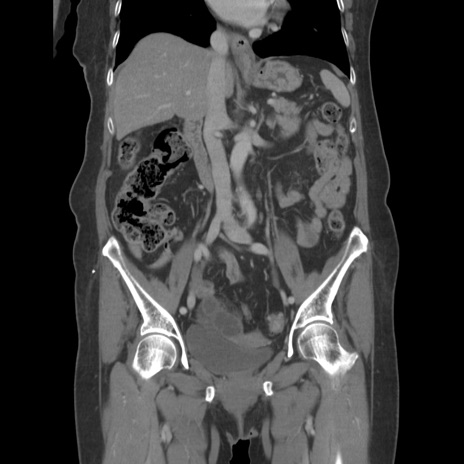

横断像

【症例】80歳代女性

【主訴】下腹部痛

【現病歴】約8時間前より下腹部痛の出現あり、救急外来受診。

【既往歴】両側付属器切除

【身体所見】意識清明、下腹部正中に手術痕あり、その部位に一致して圧痛と反跳痛あり。腸蠕動音は亢進。

【データ】WBC 9300、CRP 0.15